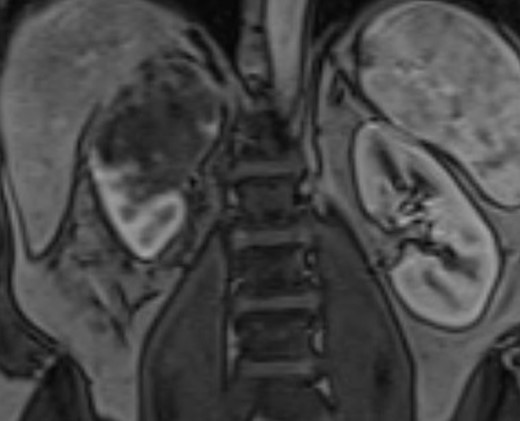

A 51-year-old white male with BMI of 29.7 was referred for gross hematuria. Renal ultrasound identified right hydronephrosis and ureteroscopy demonstrated high grade T2 urothelial carcinoma. CT and MR imaging revealed an 8 cm upper pole infiltrative tumor which obliterated the right renal vein without caval thrombus (Figs 1 and 2). There was no evidence of metastasis on CT chest. The preoperative estimated glomerular filtration rate was 71 ml/min/1.73 m2. Multidisciplinary review was undertaken and a radical nephroureterectomy and lymph node excision was recommended without neoadjuvant chemotherapy.

Coronal MRI of the abdomen/pelvis demonstrating no evidence of caval thrombus. The right renal vein was not visible on MRI.